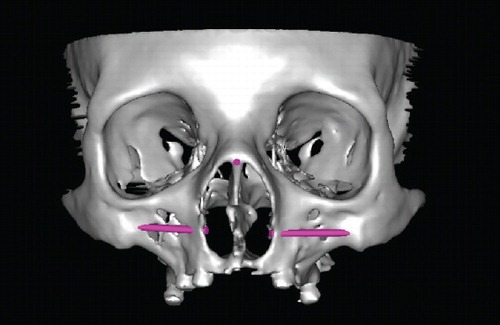

Zygomatic Implants supporting facial prostheses really improve the quality of life for patients following rhinectomy. Here is a case from a group in Norway demonstrating the secondary placement of zygomatic and dental implants in order to retain a nasal prosthesis, here with the use of small magnet abutments. The complexity of undertaking this secondarily in our view with computerised planning and surgigide construction together with the delay in providing a retentive solution is the reason why our approach is always to place implants at the time of resective surgery.